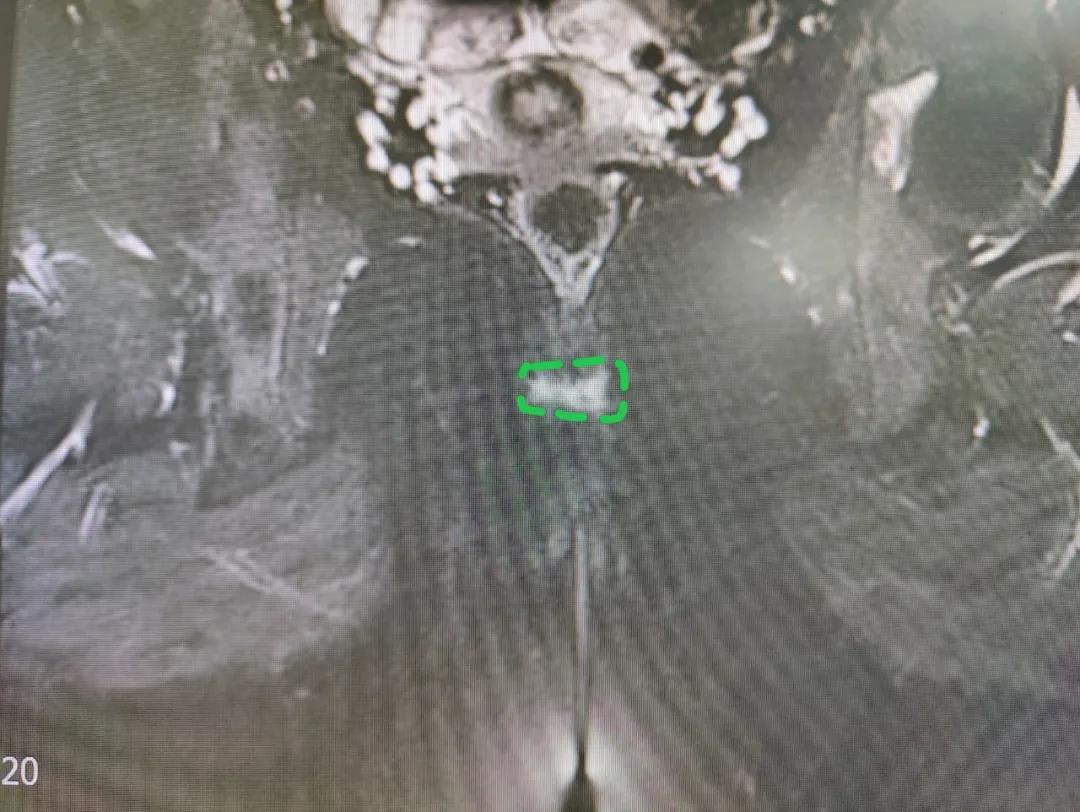

陈文平主任了解翟女士情况后,对疼痛进行了评估,结果显示翟女士忍受的疼痛等级已达到了10分,谁都没法想象,这三年,翟女士是怎么扛过来的。根据诊断指南,一一排查,在完善肛管核磁后,发现翟女士骶尾部存在有一个3mm感染病灶,最终明确诊断为骶尾部感染。